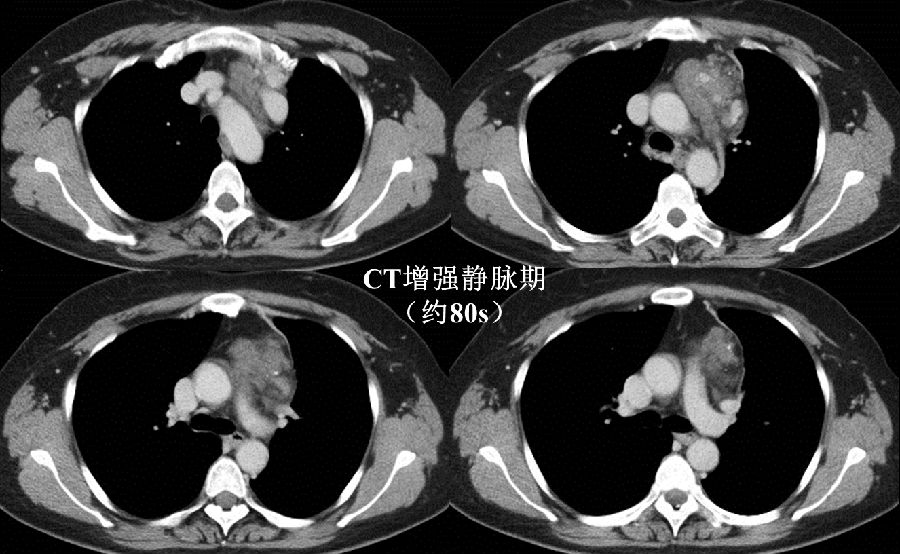

病例提供 伍建林教授(大连大学附属中山医院) 简要病史 患者,女,45岁 主诉:胸前区疼痛、胸闷3年,加重半月余。 现病史:3年前患者无明显诱因出现间断性胸前区疼痛、胸闷,伴后背部疼痛,运动后上述症状加重,无呼吸困难,无头晕、头痛,于当地医院行冠脉造影示:冠状动脉粥样硬化,具体治疗不详,出院后自服硝酸甘油,上诉症状可缓解。半月前,患者上诉症状加重,于当地医院行胸部CT检查发现:左前上纵隔肿物,并于我院门诊以“纵隔肿物”收入院进一步诊治。病来无咀嚼无力,无气短,无咯血,无关节疼痛,无进行性消瘦,无恶心、呕吐、低热盗汗等。 既往史:胸背部脂肪瘤术后8年;高血压病史4年,自服药物治疗效果良好;否认其他病史。 一般查体与专科查体无明显异常。 影像资料